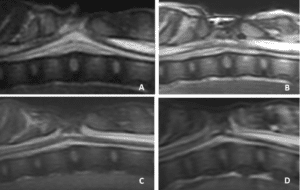

L’imagerie en coupe par résonnance magnétique ou myéloscanner est l’examen de choix pour localiser et catégoriser le type d’anomalie vertébrale et médullaire associé.